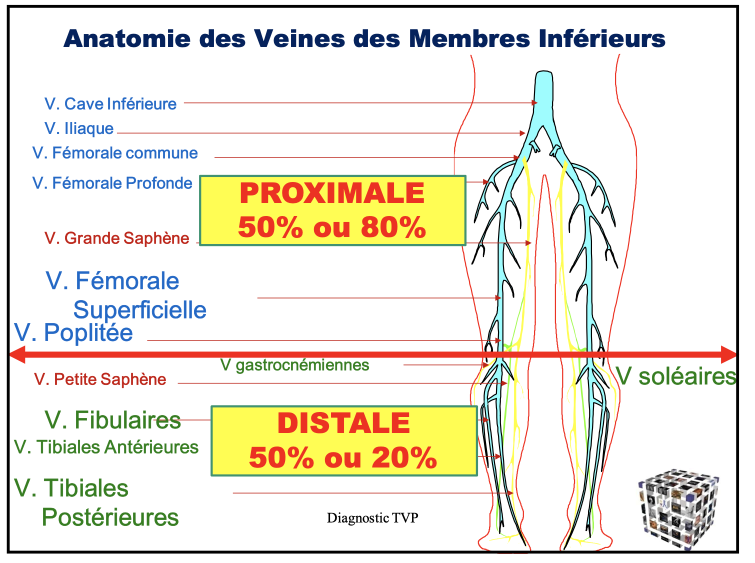

Veine cave Inf

- A faire avec sonde abdominale

Veines iliaques

- A faire avec sonde abdominale

Veine fémorale commune

Veine fémorale superficielle

Veine poplitée

Veines Jambières

Schema

Veines jumelles (gastrocnemiennes)